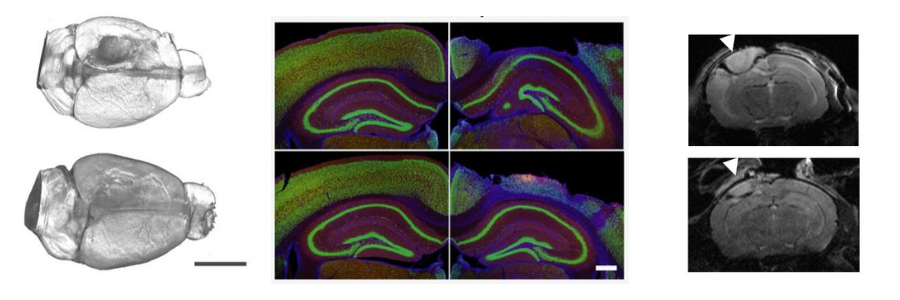

Left: The top image shows an untreated mouse brain after a controlled impact, the site of damage can be seen by the dark circular impact site. The bottom brain is from a treated mouse 14 days after the impact, the absence of a visible impact site shows the success of the treatment in preventing brain tissue loss.

Middle: These immunofluorescence staining images show how the treatment has reduced the amount of damage after traumatic brain injury when mice were pre-treated with the IL2 treatment. The top layer of brain tissue is visibly thicker in the bottom right image compared to top right. Each row shows the uninjured brain hemisphere (left) and the injured hemisphere (right). The top row shows an untreated brain while the bottom row shows a treated brain, with less damage occurring in the injured hemisphere.

Right: A magnetic resonance imaging (MRI) scan of the brains of two mice after a controlled impact to create a traumatic brain injury. The arrow shows there the impact was made, the grey area below the arrow shows the size of the lesion. The amount of brain swelling is visibly reduced in the brain of the treated mouse (bottom).

These immunofluorescence staining images show how the treatment has reduced the amount of damage after traumatic brain injury when mice were pre-treated with the IL2 treatment. The top layer of brain tissue is visibly thicker in the bottom right image compared to top right. Each row shows the uninjured brain hemisphere (left) and the injured hemisphere (right). The top row shows an untreated brain while the bottom row shows a treated brain, with less damage occurring in the injured hemisphere.